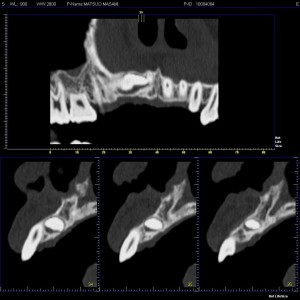

で、レントゲン写真を見ると、上顎右側の犬歯が埋伏し、あさっての方向を向いています。

(レントゲン写真)

仮歯をセットし、後日より詳しい診断のため、CT を撮影しました。

(CT axial)

(CT cross cut)

CT の画像では、犬歯は口蓋側に横たわり、犬歯の尖頭は切歯の根尖付近に、歯根は第二小臼歯の根尖付近に位置している埋伏歯であることが分かります。

矯正治療の妨げになるため、本日抜歯となりました。

さて、パノラマレントゲンは、3次元のものを2次元の画像にしているワケで、そこには奥行きがあり情報量には自ずと限界があります。

もちろん CT 画像も100%というワケではなく、実際に肉眼で確認したとき、良くも悪くも若干の違いはありますが、見てのとおり情報量はまるで違いますね。

当然 手術手技によっても差が出ると思いますが、切開・剥離、骨削の範囲も最小限になるので、予知性の高い安心な手術を行う事が出来ます。

結構シビアなケースでしたが、CT のお陰で予定時間内に終了

お疲れ様でした。